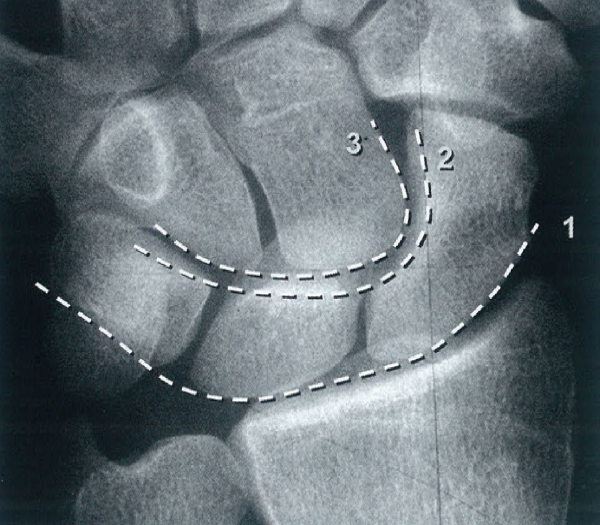

Gilula·s线,任意一条弧线的中断或台阶表明有明显的腕关节排列异常

微信截图_20170409230347.png